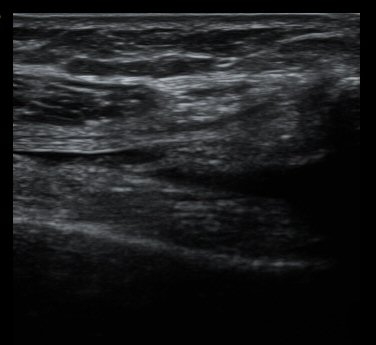

¹«¸­ ³»ÃøºÎÀδë Á¾´Ü¸é°Ë»ç¿¡¼­ ³»ÃøºÎÀδë Ç¥Ãþ±ÙÀ§ºÎ Àú¿¡ÄÚ ºÎÁ¾ ¹× ½ÉÃþ±ÙÀ§ºÎ ºÎºÐÆÄ¿­ÀÌ

°üÂûµÊ(±×¸² 3, 4).